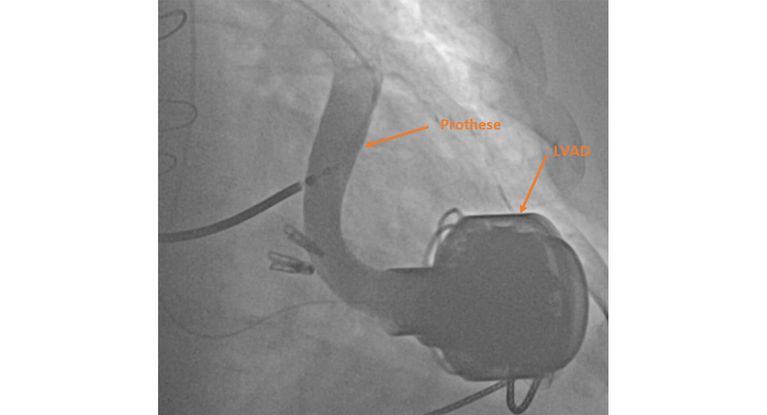

Angiographie: nach Stenting der Prothese ist keine Stenose mehr erkennbar.